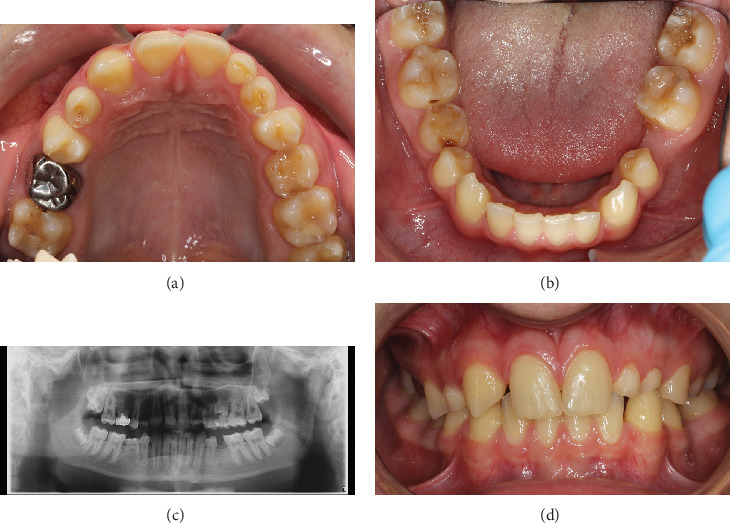

本病例报告报告了由于受术者骨容量不足,牙齿移植和无移植物窦提升是如何结合的。一颗未出牙的智齿被自动移植以取代缺失的上前磨牙。首先,将供牙暴露并轻轻移动。在受体部位,上颌窦下有一薄层骨。侧窗技术用于窦内提升。在提升窦底粘膜后,准备骨以匹配供体牙的尺寸。粘膜轻度穿孔。供体牙移至受体位置,颊根部分骨覆盖缺失。移植的牙齿用缝线固定。在4年的随访对照中,移植牙完全萌出,无任何临床或影像学病理征象。如果移植供牙的牙周韧带处理得当,可以保存和促进牙槽骨的生长。在随访中,供体牙的牙根周围明显形成了新骨。在上颌前磨牙区成功移植发育中的牙齿是可能的,尽管最初的骨容量不足。

This case report reports how tooth transplantation and a graft-free sinus lift were combined due to insufficient bone volume at the recipient site. An unerupted wisdom tooth was autotransplanted to replace a missing upper premolar. First, the donor tooth was exposed and gently mobilized. At the recipient site, there was a thin layer of bone under the maxillary sinus. The lateral window technique was used in the sinus lift. After elevating the mucous membrane of the sinus floor, the bone was prepared to match the measures of the donor tooth. The mucous membrane was slightly perforated. The donor tooth was moved to the recipient site, and the buccal root partially lacked bony coverage. The transplanted tooth was fixated with sutures. At the 4-year follow-up control, the transplanted tooth was fully erupted without any clinical or radiographical signs of pathology. If the periodontal ligament of the transplanted donor tooth is delicately handled, it can preserve and facilitate the growth of the alveolar bone. During follow-up, it was obvious that new bone had formed around the roots of the donor tooth. It is possible to successfully transplant a developing tooth in the maxillary premolar region, although the initial bone volume is insufficient.